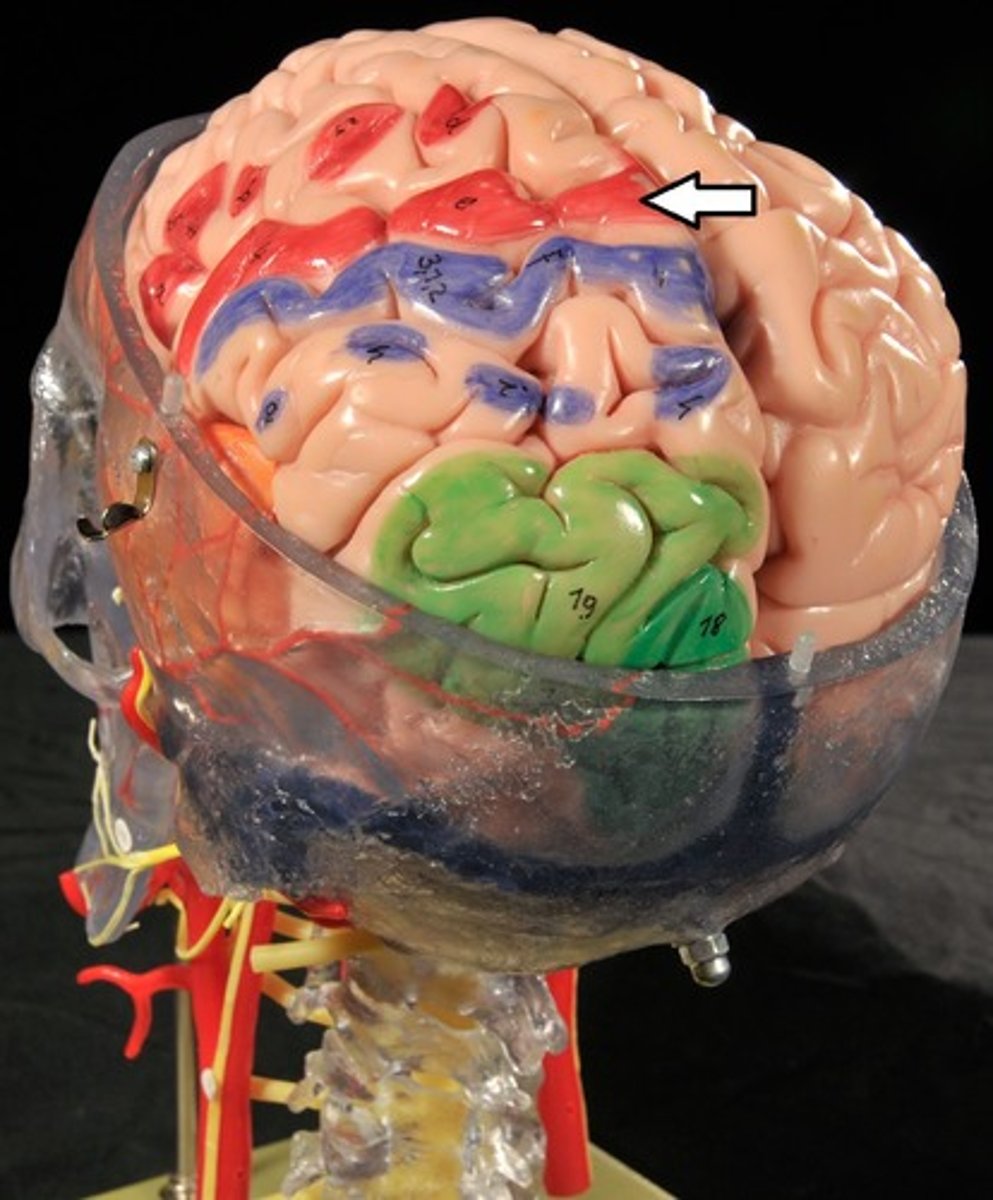

Cerebrum: Sulci and Gyri

Central Sulcus,

Precentral gyrus,

Postcentral gyrus

Central Sulcus

Precentral Gyrus

Postcentral Gyrus

Frontal Lobe

Primary (somatic) motor cortex

Parietal Lobe

Reception and evaluation (integration) of sensory information except for smell, hearing, and vision

Frontal lobe: motor cortex

1) Controls precise or skilled voluntary movements of our skeletal muscles

2) Also learned motor skills (repititious or patterned nature) like playing an instrument or typing

3) Is contralateral: left primary motor cortex controls muscles on right side of body & vice versa

Clinical: damage to frontal lobe

Damage to localized areas of frontal lobe (such as from a stroke) paralyzes body muscles controlled by those areas.

Only voluntary control is lost, however, as muscles can still contract reflexively.